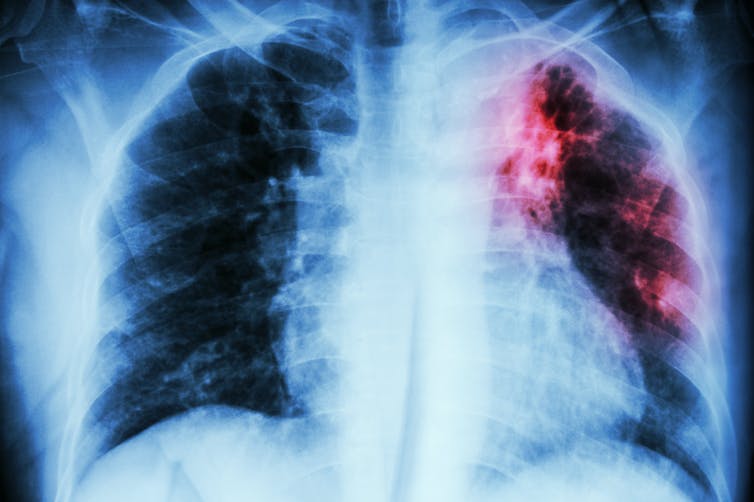

Tuberculosis y covid-19 son enfermedades infecciosas de transmisión aérea. Afectan mayoritariamente al sistema respiratorio y manifiestan una tríada clásica de síntomas: tos, fiebre y disnea. Foto: Shutterstock Puwadol Jaturawutthichai

Tuberculosis y covid-19 son enfermedades infecciosas de transmisión aérea. Afectan mayoritariamente al sistema respiratorio y manifiestan una tríada clásica de síntomas: tos, fiebre y disnea. Esto dificulta inicialmente el diagnóstico diferencial, especialmente en países con alta incidencia de tuberculosis.